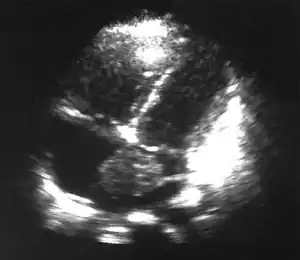

In obstructive shock, CO is decreased, CVP is elevated, SVR is increased, and PAOP is increased which is similar to cardiogenic shock. Obstructive shock can most easily be differentiated from cardiogenic shock by considering the greater clinical picture in the context of the PA catheter data (or echocardiography)